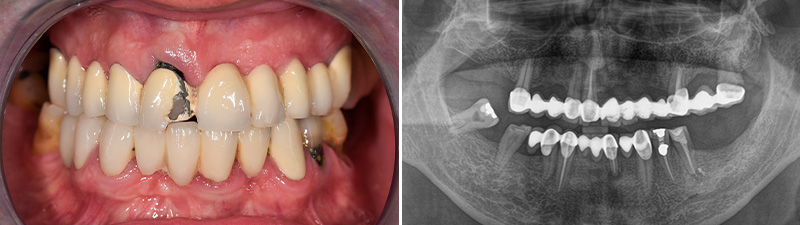

Un patient de 60 ans se présente pour un examen et une consultation en vue d’une réhabilitation prothétique du maxillaire supérieur. L’examen clinique et une radiographie panoramique révèlent un ancien bridge métal-céramique, des dents avec de profondes poches parodontales, et des caries sur les dents piliers. Plusieurs options thérapeutiques sont proposées. Il opte pour une réhabilitation implantaire par la méthode « All-on-4 ».

Fig. 01 : patient avant la réhabilitation implantaire par la méthode « All-on-4 ».

Fig. 02 : photographie intraorale préopératoire et radiographie panoramique préopératoire.